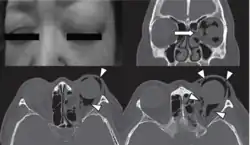

The diagnosis of orbital emphysema is usually made by physical examination of the eyelids,[11][35] and, or by computer tomography (CT).[11][6][3][15][34][37][38]

Physical examination

Physical examination of the eyelid can be done by the palpation for the pathognomonic cracking, crepitation,[11] and tense tissue[35] on the upper and lower eyelids. The findings of the examination are supported with the medical history of the patient and confirmed with orbital CT.[6]

Computed tomography (CT)

Computed tomography is effective and sensitive in the diagnosis of orbital emphysema,[3][37] as it can confirm the anatomical location and size of air, bony defects, indentation of the eyeball, and the condition of the optic nerve, as well as the presence of any extraocular muscle entrapment and herniation of preorbital fat into the sinus cavities.[3][15][38] The location of the orbital emphysema is present near the site of the fracture.[1][3] The scans are usually taken along the transverse plane. Transverse images allow the evaluation of fractures in medial and lateral orbital walls. By reformatting these transverse images or taking coronal images, the examination of orbital floor and roof is permitted. Helical scanning is preferred as it has a lower imaging time and radiation dose comparing to conventional scanning, especially when reforming transverse helical scans into coronal images.[3] The staging of orbital emphysema can then be determined with visual acuity examination and ophthalmoscopy.[6] A disadvantage of using a CT scan is that when detecting air after orbital trauma, the presence of a wooden foreign object can give a false positive result of orbital emphysema. The wooden object can mimic the presence of orbital emphysema. Therefore, patients’ medical history is crucial in making the correct diagnosis.[3]